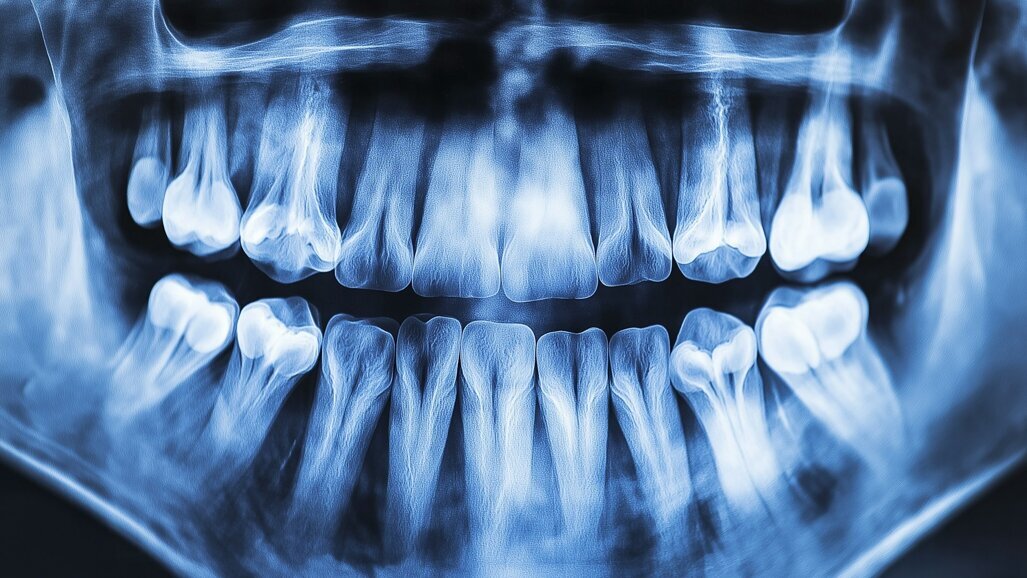

Panoramic radiograph analysis:

Missing 17, 26, 38, 36, 46 and 47.

Retained root 16, 45.

Poor prognosis 26.

Increased vertical bone loss especially 11,21 (only ~30% left)

Missing 18, 16, 25,26, 28, 36, 47 and 48.

20-30% vertical bone loss upper anterior region.